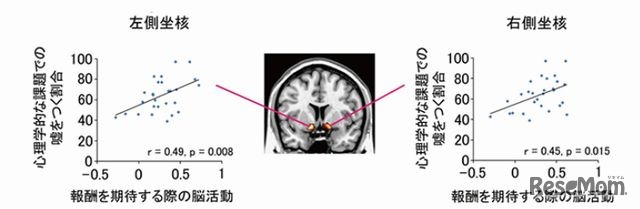

京都大学は8月6日、正直者と嘘つきの脳の仕組みの違いを解明したと発表した。「側坐核(そくざかく)」と呼ばれる脳領域の活動が高い人ほど、嘘をつく割合が高かった。脳の働きの個人差によって、人間の正直さがある程度決まることを示したのは世界初だという。